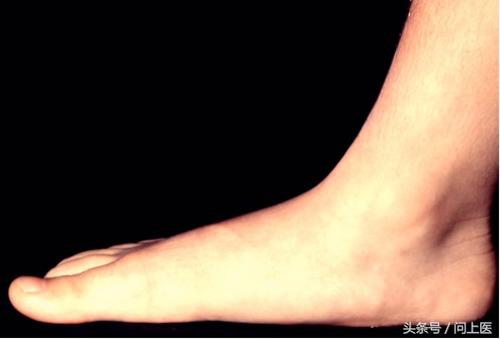

8 / 8 扁平足(平足)

如图所示,当脚底可以完全或大部分与地面接触时,就可判定为扁平足。受伤后或因健康问题,如类风湿性关节炎等会导致扁平足。加强脚的锻炼,穿具有良好的足弓支撑的鞋或矫形器可以帮助改善扁平足。